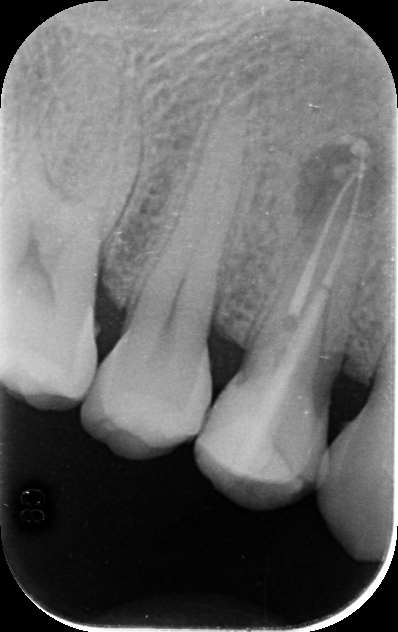

- After 10 days, at the second appointment, I removed the medicament and filled the canals with permanent root canal material.

- I restored the tooth with composite filling and discussed with the patient that placing a crown immediately was not necessary. Instead, I advised waiting one year to assess healing before considering a crown, to avoid unnecessary expenses.